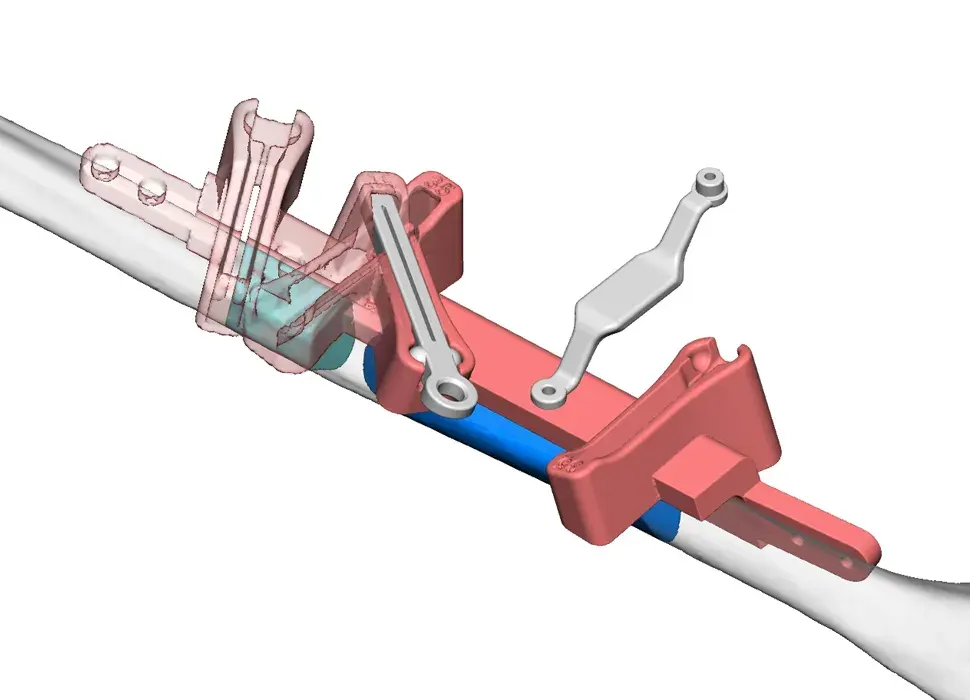

3D Systems' VSP® surgical planning solutions for craniomaxillofacial (CMF) applications received FDA clearance as a service-based approach to personalized surgery over 10 years ago.

3D Systems and Stryker Corporation have partnered to provide surgeons with best-in-class products and services for craniomaxillofacial surgeries. As a leader in personalized healthcare solutions, 3D Systems has planned and delivered devices for more than 140,000 patient-specific cases. The Stryker Craniomaxillofacial business specializes in providing patient-specific options and innovative solutions that help drive efficiencies in surgical suites. The combination of Stryker’s specialized team and advanced implants with 3D Systems' cutting-edge 3D printing technologies and expert consulting services positions both companies to provide a superior level of service to healthcare professionals who use these revolutionary solutions.